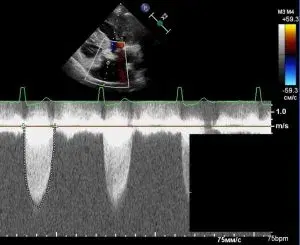

Learn how to evaluate the aortic valve stenosis with echocardiography.

Manage possible difficulties and pitfalls during aortic valve stenosis evaluation.